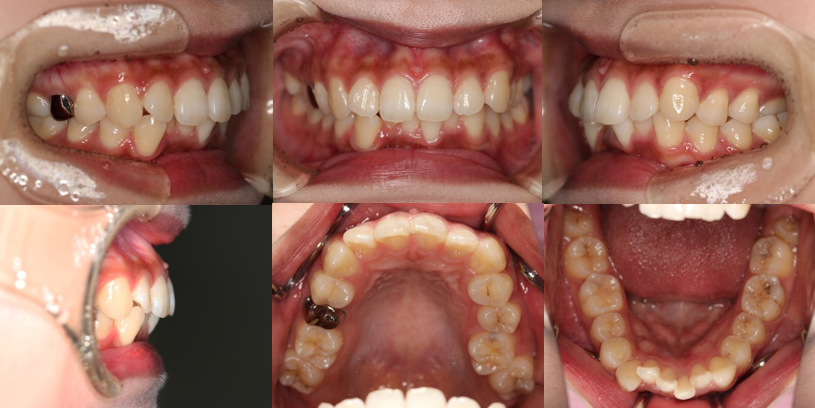

上下顎前突(やや口ゴボ)+叢生(歯のガタガタ)+過蓋咬合(かみ合わせが深い)

Before